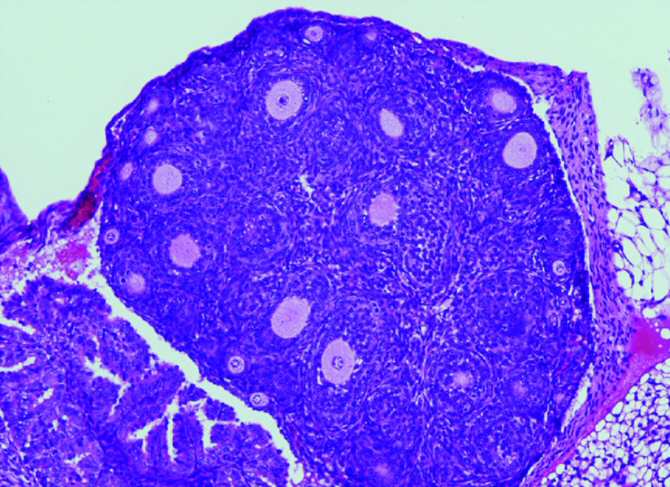

Reducción en el número de folículos ováricos (causante de la insuficiencia ovárica prematura) en los ratones con la variante humanizada en FOXL2. (Imagen: Centro de Investigación del Cáncer (CSIC-USAL))

“Nuestro grupo -señala Elena Llano, ha desarrollado por primera vez un modelo de ratón que alberga en su gen FOXL2 la variante C134W, presente en los tumores humanos, para así poder evaluar in vivo el papel desconocido de FOXL2 en la iniciación y desarrollo tumoral. Para nuestra sorpresa, estos ratones presentan la hipoplasia del párpado observada en el síndrome de blefarofimosis. Curiosamente, las hembras con dicha mutación presentan una fertilidad reducida y lo que es más relevante todas desarrollan AGCT espontáneamente. Es decir, progresan gradualmente de ovarios anormales con células de la granulosa aberrantes a ovarios con hiperplasia estromal y atipia, que finalmente dan lugar a la aparición de tumores ováricos en la totalidad de los animales antes de los 18 meses de edad. Por tanto, este proceso parece estar impulsado únicamente por la presencia de la variante FOXL2”.